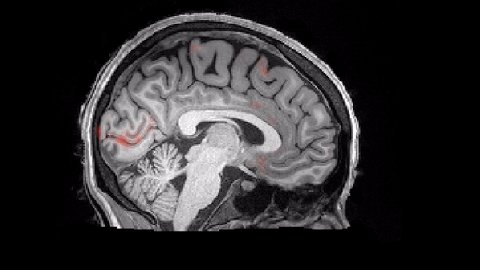

However, new research published in the journal Science may have just uncovered what’s really going on in our brains while we dream about being late for an exam because our teeth fell out. Our brains may actually be taking a bath in cerebrospinal fluid (CSF), a watery substance that washes out all the gunk that accumulates in our brains over the course of the day.

Lead author Laura Lewis and colleagues wanted to get a comprehensive picture of how the brain was clearing these waste products out overnight, so they recruited several participants to wear EEG caps to measure neural activity while also instructing the participants to sleep within an MRI to measure CSF activity — which isn’t an easy task.

Fortunately, the participants did manage to get to sleep, revealing a never-before seen phenomenon take place in our brains every night. During a phase of non-REM sleep called slow-wave sleep, Lewis and colleagues observed an ebb and flow of electrical activity and CSF levels.

“First you would see this electrical wave where all the neurons would go quiet,” said Lewis. A few seconds afterwards, Lewis and colleagues saw that “there are these really large, slow waves occurring maybe once every 20 seconds of CSF washing into the brain.”

As the brain’s neurons go quiet after a slow wave, they require less oxygen. Since they require less oxygen, less blood flows to these regions of the brain. With less blood, there’s more space for CSF to rush in and scrub the brain of its waste products. “We’ve known for a while that there are these electrical waves of activity in the neurons,” said Lewis, “But before now, we didn’t realize that there are actually waves in the CSF, too.”